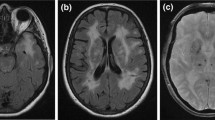

She had an MRI scan which showed an acute infarct in the midbrain with high signal on diffusion-weighted imaging (Fig. 24.1, 1-4), as well as extensive white matter changes with prominent involvement of the anterior temporal poles. (Fig. 24.1, 1-2, 1-3).

(inset 1-1). Pedigree of clinical case 1. Although II.1, II.2 and III.1 had neurological symptoms, there was no clear history of stroke or dementia in the family. (1-2) MR T2-weighted imaging showing white matter intensities involving the anterior temporal poles (arrowed) and (1-3) external capsules. (1-4) Midbrain lesion shown on MR diffusion-weighted imaging, and (1-5) apparent diffusion coefficient imaging (arrowheads). (Copyright Hugh Markus)

Her mother was alive at age 83, with a history of migraines and bipolar disease . Her father died at age 72, having had possible complex partial seizures. Her identical twin sister had a history of migraine with aura. Despite the absence of a clear family history of stroke or dementia, the classical involvement of the anterior temporal poles and possible family history led to suspicion of CADASIL (Fig. 24.1). Genetic testing confirmed a p.Arg90Cys mutation on exon 3 of the NOTCH3 gene.